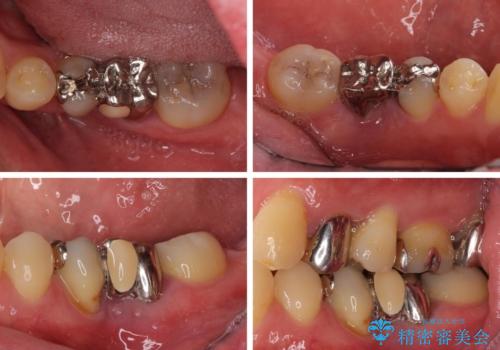

- 奥歯の痛みと前歯のデコボコを気にして来院された患者様です。

左右下顎の大臼歯は、ともに歯根が破折しており、抜歯が必要な状態でした。

咬み合わせは受け口傾向であり、上顎前歯の叢生が顕著であったことから、第1小臼歯抜歯による矯正治療も検討しましたが、下顎大臼歯を左右ともに抜歯するため、非抜歯による矯正治療を行うこととしました。